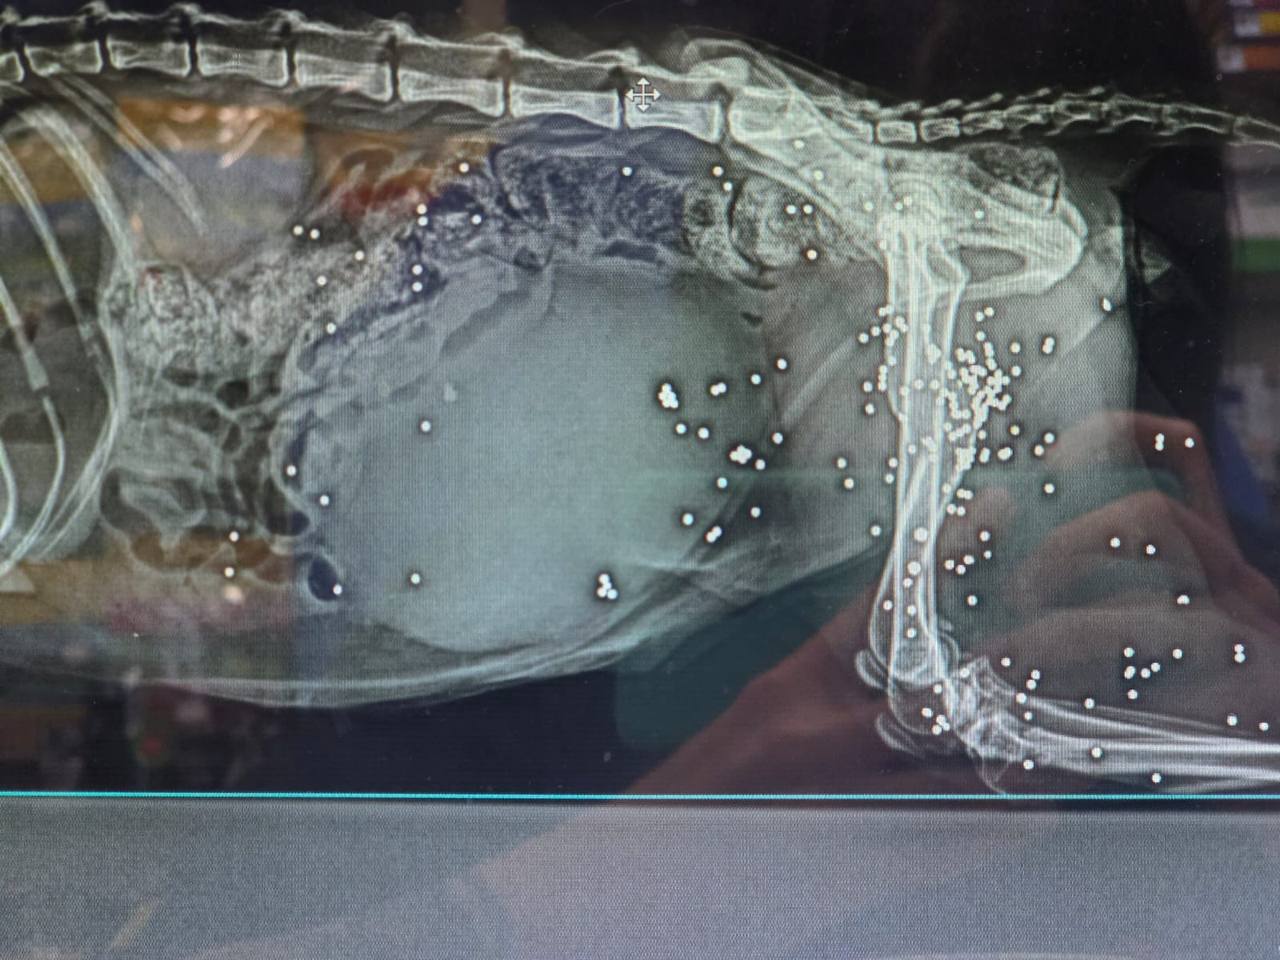

@yulya_yulya_yulya_yaМножественные пулевые ранения , в том числе в голову. Внутреннее кровотечение 😵💫Может и не машина сбила. Найден на дороге… завтра будут новости.

После 130, врач перестала считала пули.

Не хотела кидать в чат, но напишу, что врач, когда взяла кровь на анализ, анализы плохие по многим параметрам. Решила рентген сделать на всякий случай, чтобы понять в чем дело и помочь чем-то, сем можно. И получила такой результат.

Теперь хоть каждого проверяй на рентгене…

@ARAlenaRadЯ не разбираюсь, в заключении напишет врач наверное точнее. Мне сказала bullets. 🤷♀️